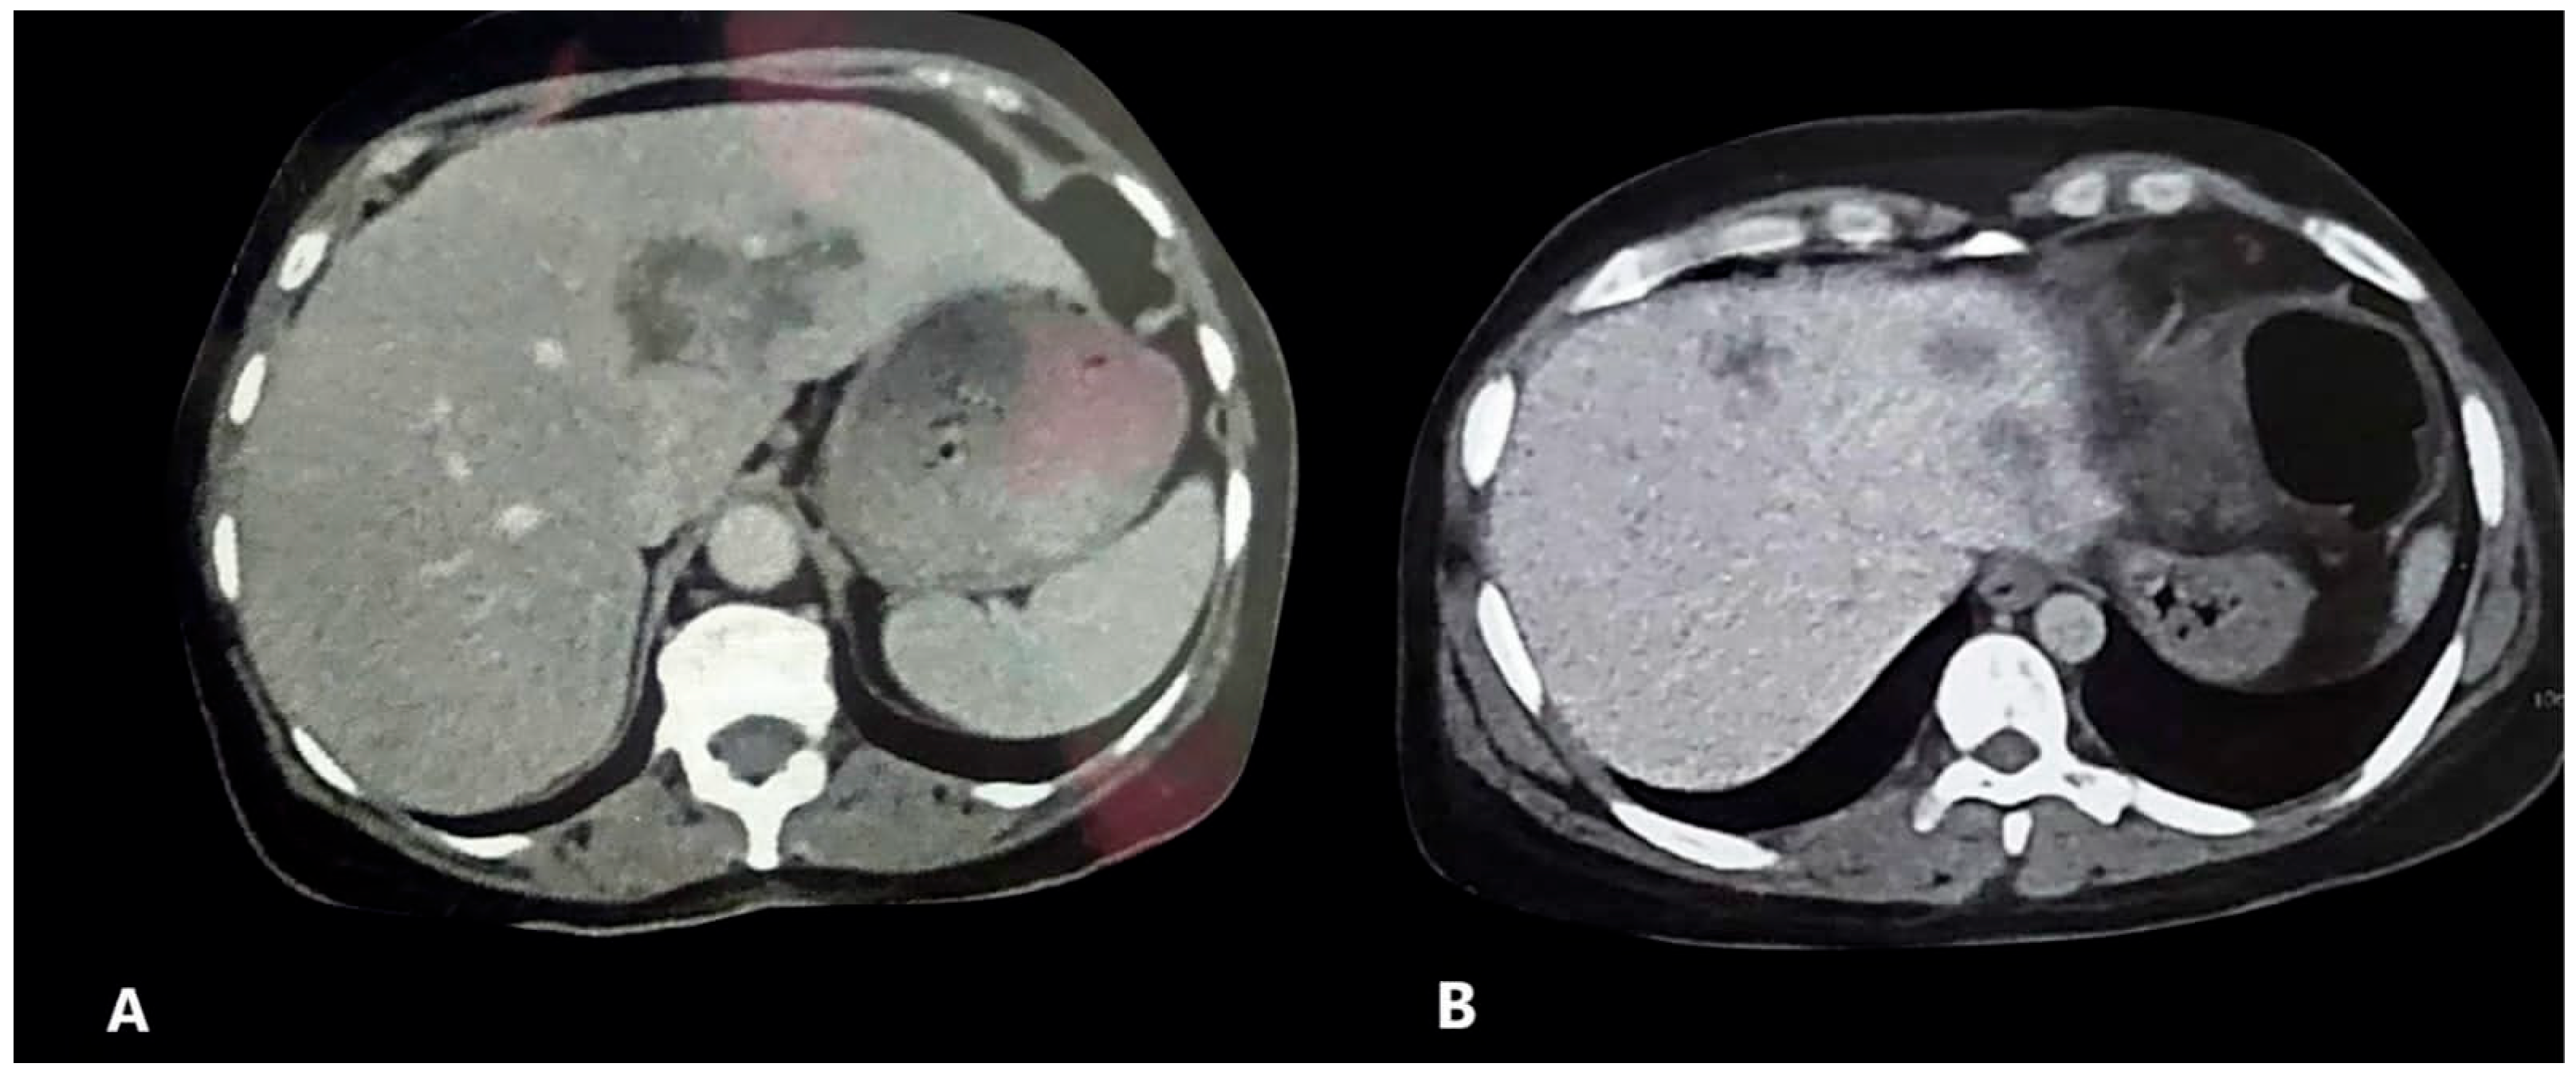

| HFL | 25 (38.5) | 8 (12.3) | 0.000 * | 41 (57.7) | 6 (8.5) | <0.001 * |

| Radiological response | 18 (27.7) | 35 (49.3) | 0.036 * |